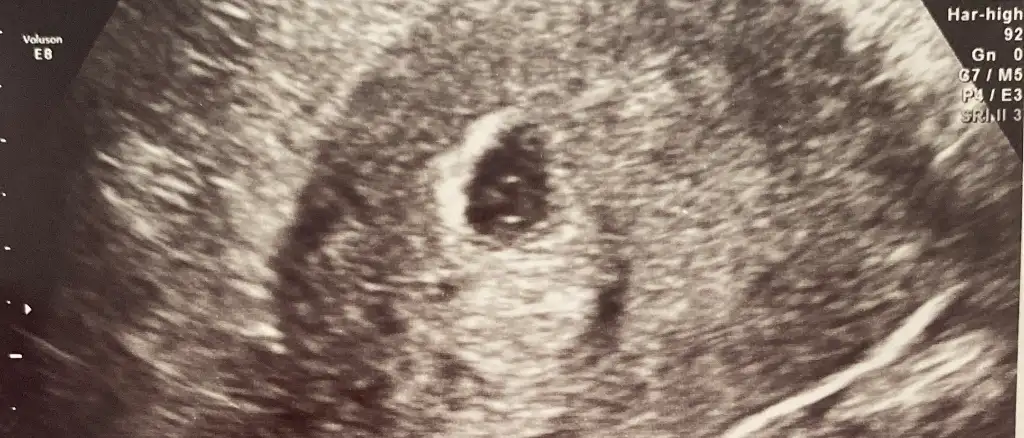

Erkek bence canım13 haftalik bakarmiisniz karindan

Tamam işte kıza benziyorBuda 9+4

2 kızım vardı buda oğlan olsaydı KısmetTamam işte kıza benziyor